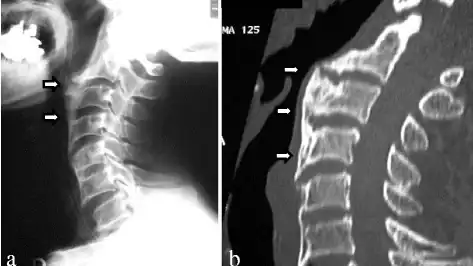

The evaluation of osteophytes can be done via radiographs[8]

a) Recurrent ossification of anterior longitudinal ligament with anterior osteophytes arrows was present from C2 to C6 b) computed tomographic images of the cervical spine